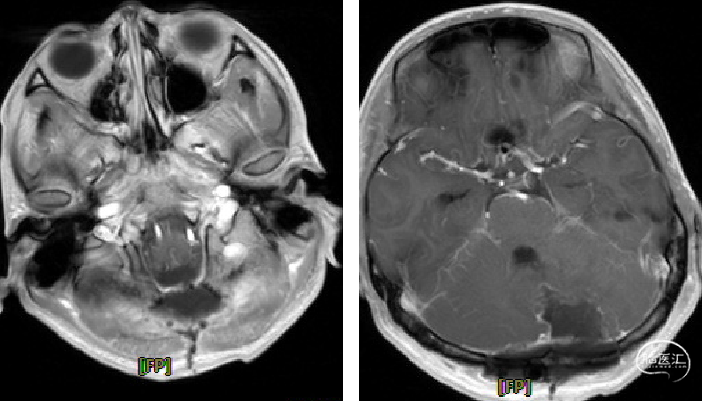

术前CT

image.png